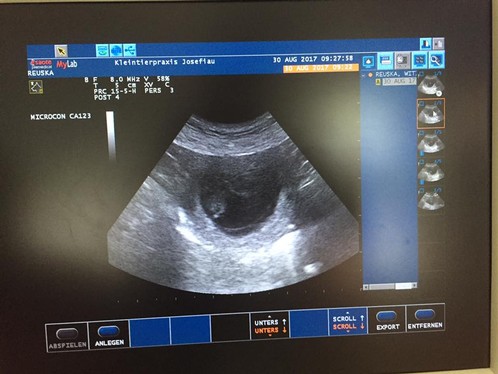

Today Ruska revealed her secret: We are expecting puppies around 5th of october